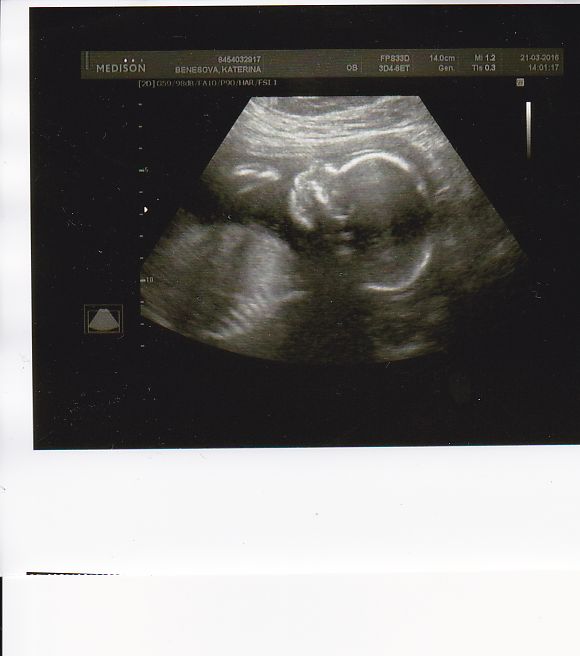

Tak screening za námi. Vše v pořádku. I když si pan doktor tedy stěžoval, že se malý moc neukazuje. Co nám nastavoval krásně a neustále byl pindík ... :D Exibicionista jeden. Tak jsem ještě dnes musela na srdíčko na kardio, protože včera si můj gyndař netroufl popsat srdce detailněji. No kardiolog dneska páskoval taky, dokonce jsem musela šlapat schody, aby se špunt otočil, ale něco nakonec viděl, nicméně mě chce za 2 týdny znova :( Jako by toho lítání po doktorech nebylo málo :D Přikládám fotku. Jinak prďola má 445 g. :D

[876026] krásnej mrňousek :-)

[876026]já jdu na srdce zítra ,ale u mého gynekologa se to dělá automaticky sem se dozvěděla...445g tý jo, v jakém jsi týdnu ?jinak super fotečka :)a gratuluji k dobrým zprávám a k chlapečkovi...